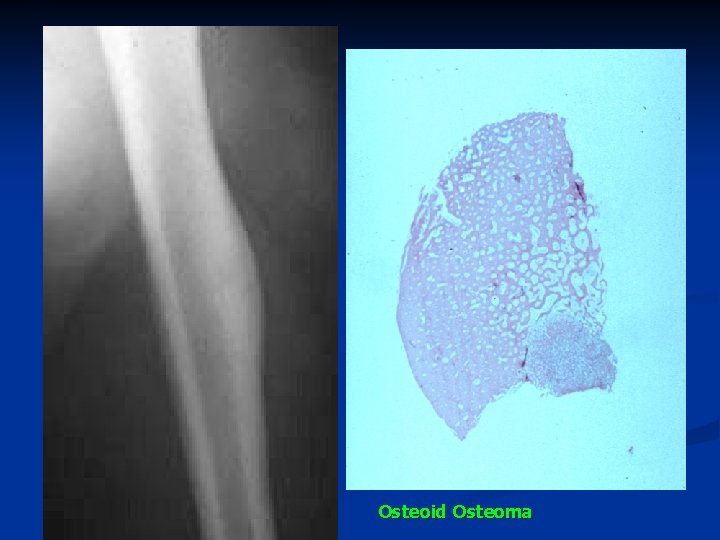

Osteoid Osteoma n n A distinctive, small (<2 cm), solitary, benign, tumorlike lesion of bone It is composed of osteoid tissue intermixed with woven bone and surrounded by reactive bony sclerosis. Osteoid osteoma most often occurs in children and young adults. A frequent presenting symptom of this condition is night pain, often relieved by aspirin, with localized tenderness in the painful area.

Osteoid osteoma is commonly located in a femur or tibia, n Radiology: n A representative x-ray picture n An osteoid osteoma shows a well circumscribed, small, round or oval, radioluscent or radiodense lesion (the nidus) n May be located in or near the cortex and surrounded by densely sclerotic bone. n

Osteoid Osteoma

n Microscopy n The nidus: n narrow trabeculae of osteoid or newly formed bone produced by osteoblasts + vascularized stroma n surrounded by a sclerotic mature bone.